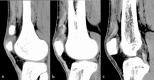

Normal development of the patella typically involves fusion of secondary ossification centers into a single bone during adolescence, with failure of fusion resulting in bipartite and tripartite patellae. In such variants, injury to incomplete ossification center fusion, though uncommon, has been reported to occur in the setting of traumatic quadriceps tendon rupture. The authors present a rare and complex case of traumatic bipartite fragment separation, patellar avulsion, and a complex partial quadriceps tendon tear confirmed surgically in a 36-year-old male. In this case, a tear in the lateral aspect of the quadriceps tendon attached to the nonfused patellar ossification center resulted in retraction of the band containing the bipartite fragment and separation of the patellar fragments, with superior displacement of the smaller bony avulsion likely due to complex attachments from the medial aspect of the quadriceps tendon. Knowledge of the classical locations of a bipartite and tripartite patella can aid in the differentiation of the anatomic variant versus patellar avulsion. Additionally, knowledge of the variable and complex nature of the quadriceps tendon aids in understanding the process of patellar avulsions and various tears, leading to the appropriate orthopedic management.